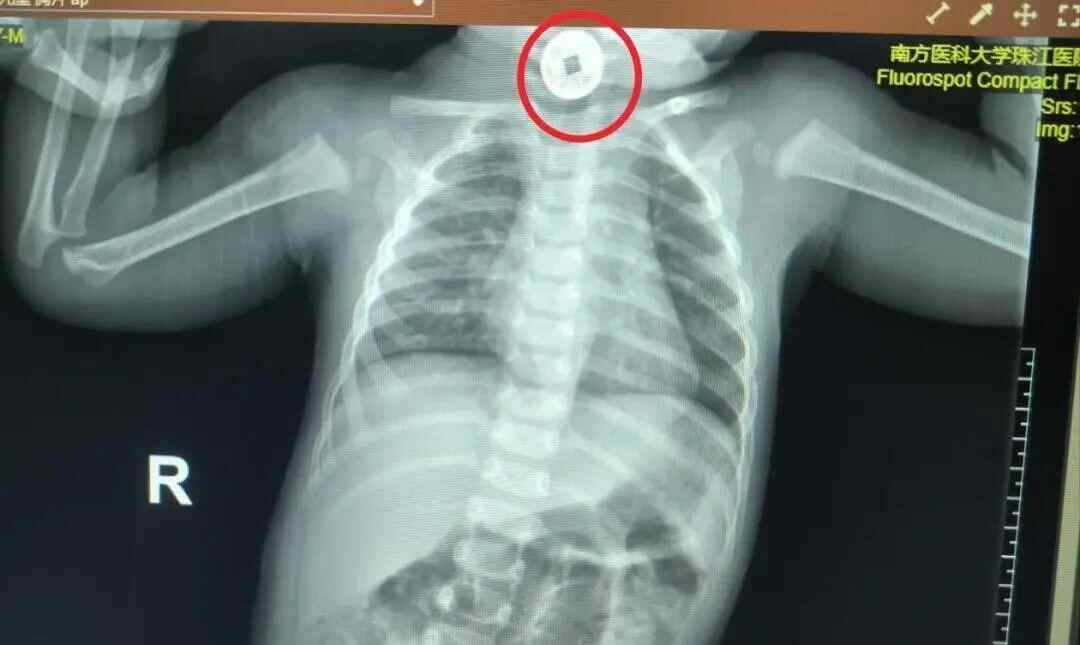

医护人员立刻启动紧急检查:通过影像学确认,一枚直径约2厘米的圆形祈福币卡在宝宝食道上段,距离咽喉仅3厘米。

这个位置很关键:食道上段狭窄,若异物滞留时间过长,可能压迫气管引发窒息,还可能损伤食道黏膜导致出血、感染。

手术过程中,陈帅君教授团队用特制的小儿异物钳小心固定祈福币,避开食道黏膜,仅用2分钟就顺利将其取出。